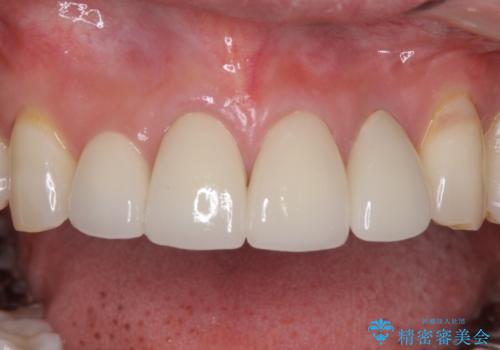

目立つ範囲である前歯4歯をオールセラミッククラウンにて補綴することとしました。

口元の印象が明るくなり、人前で気にせずに笑えるようになりました。